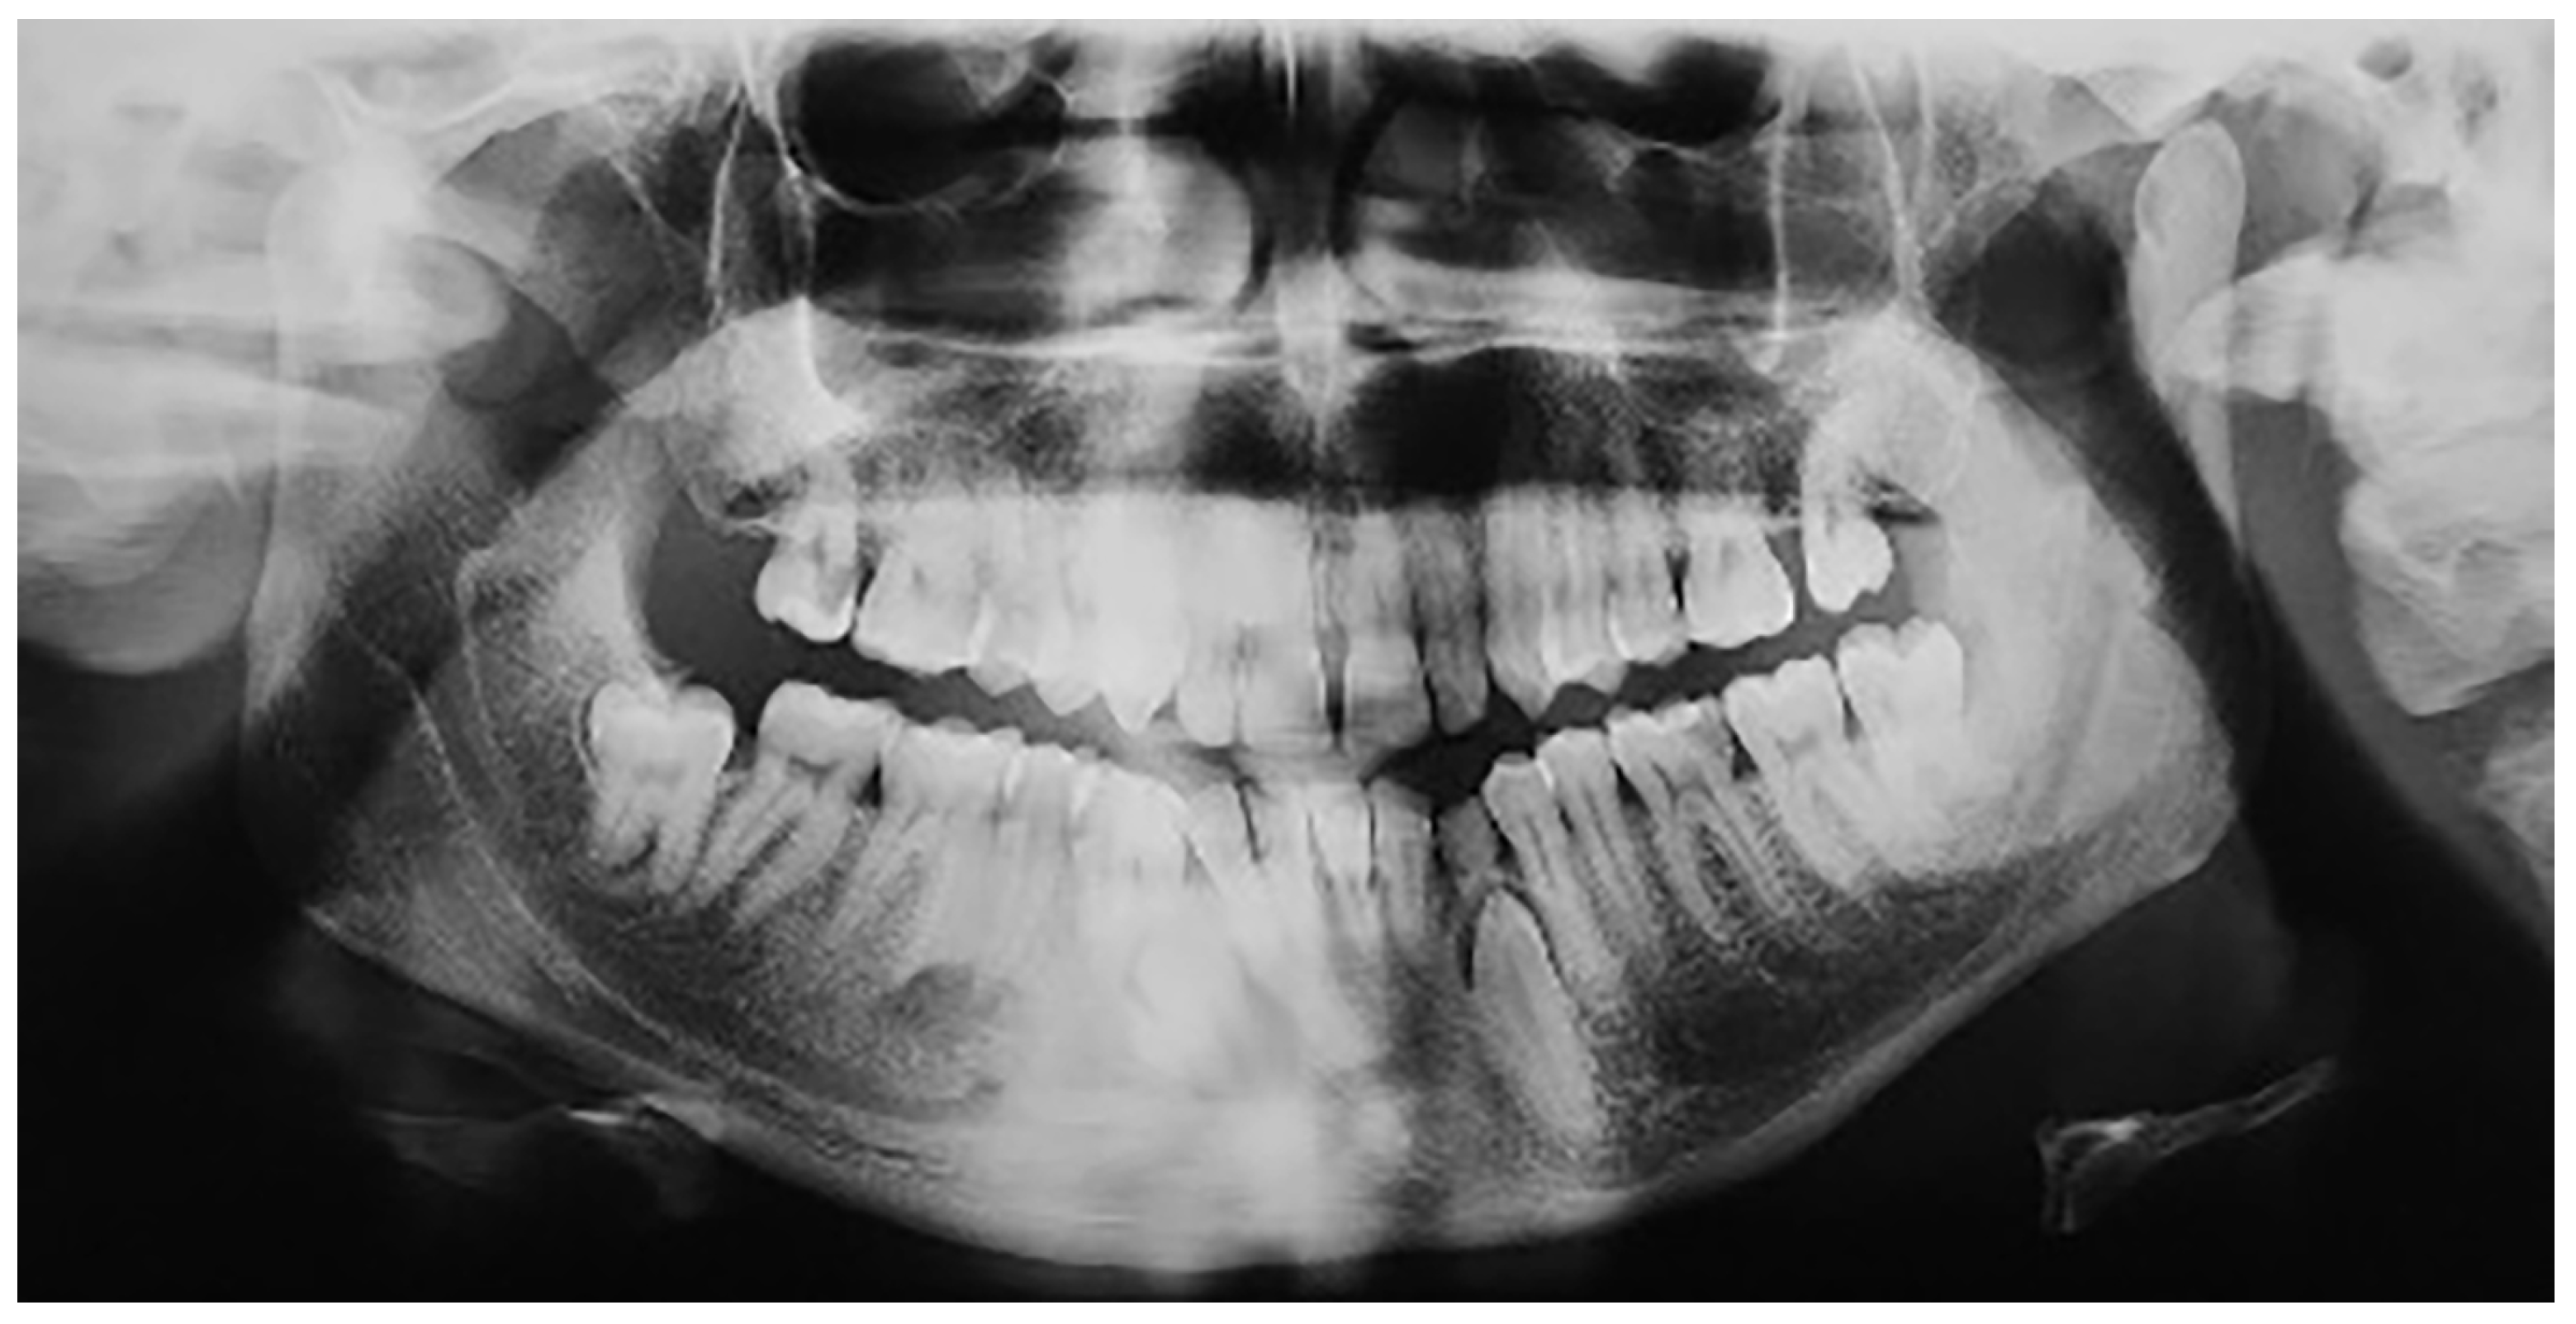

Figure 2.

Mandibular impaction of left canine and presence of a supernumerary tooth.

A total of 25 patients with mandibular canine impaction were found in Group A. Of these 25 patients, 14 were male and 11 were female. Canine impaction was bilateral in 12 patients and unilateral in 13 patients, with a total of 37 impacted permanent mandibular canine teeth. 21 impacted canines were found on the left side, and 16 canines on the right. 16 patients (64%) had retained deciduous canines at the time of diagnosis. In three cases, the impacted canines were transposed in the lateral incisor region. In one of the patients, there was a supernumerary tooth in the lateral incisor region, and the primary canine was still present in the dental arch (Figure 2). In one patient in whom the primary canine and primary lateral incisor were retained, impaction of both the lower permanent canine and lower permanent lateral incisor was noted. One patient was found to have complete impaction of all four canines. None of the patients had traumatic episodes, and none of them had systemic disorders. All the patients were asymptomatic.